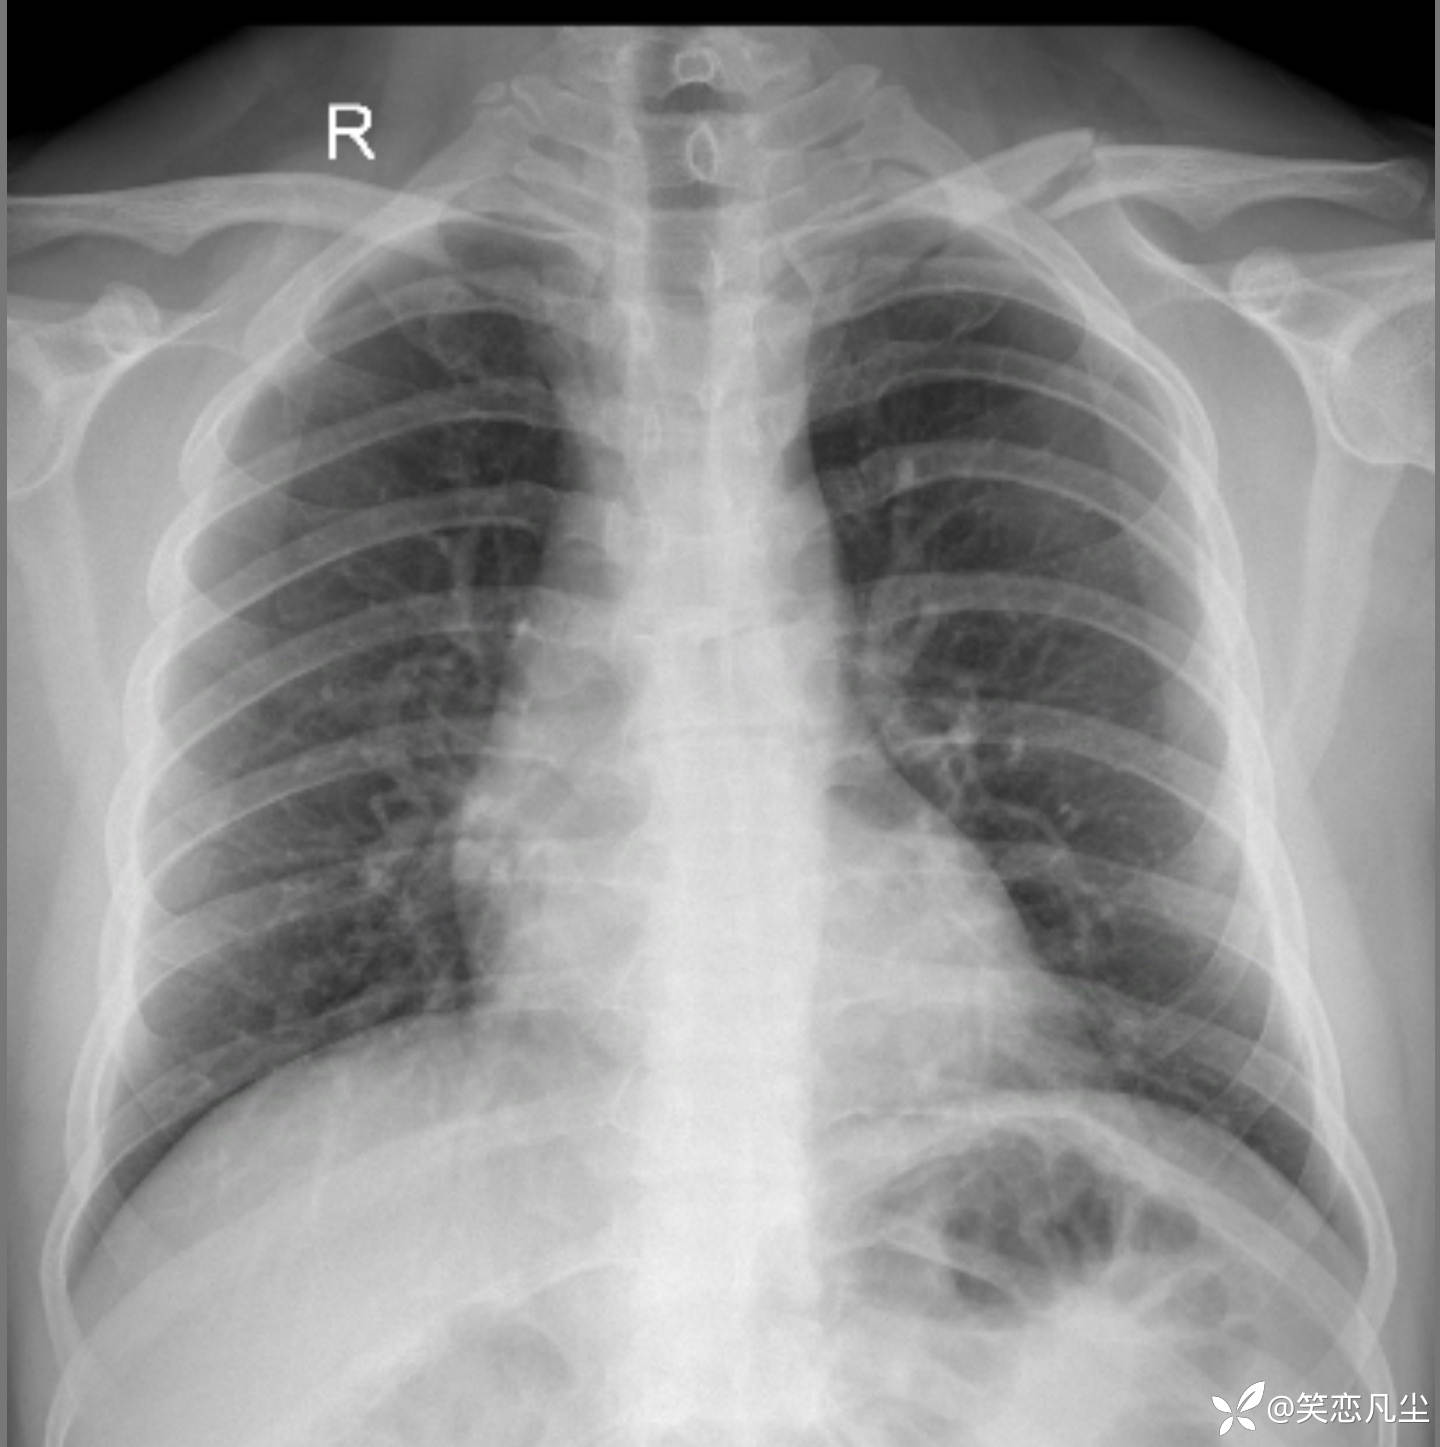

一例简单锁骨骨折

【临床诊断】:锁骨骨折